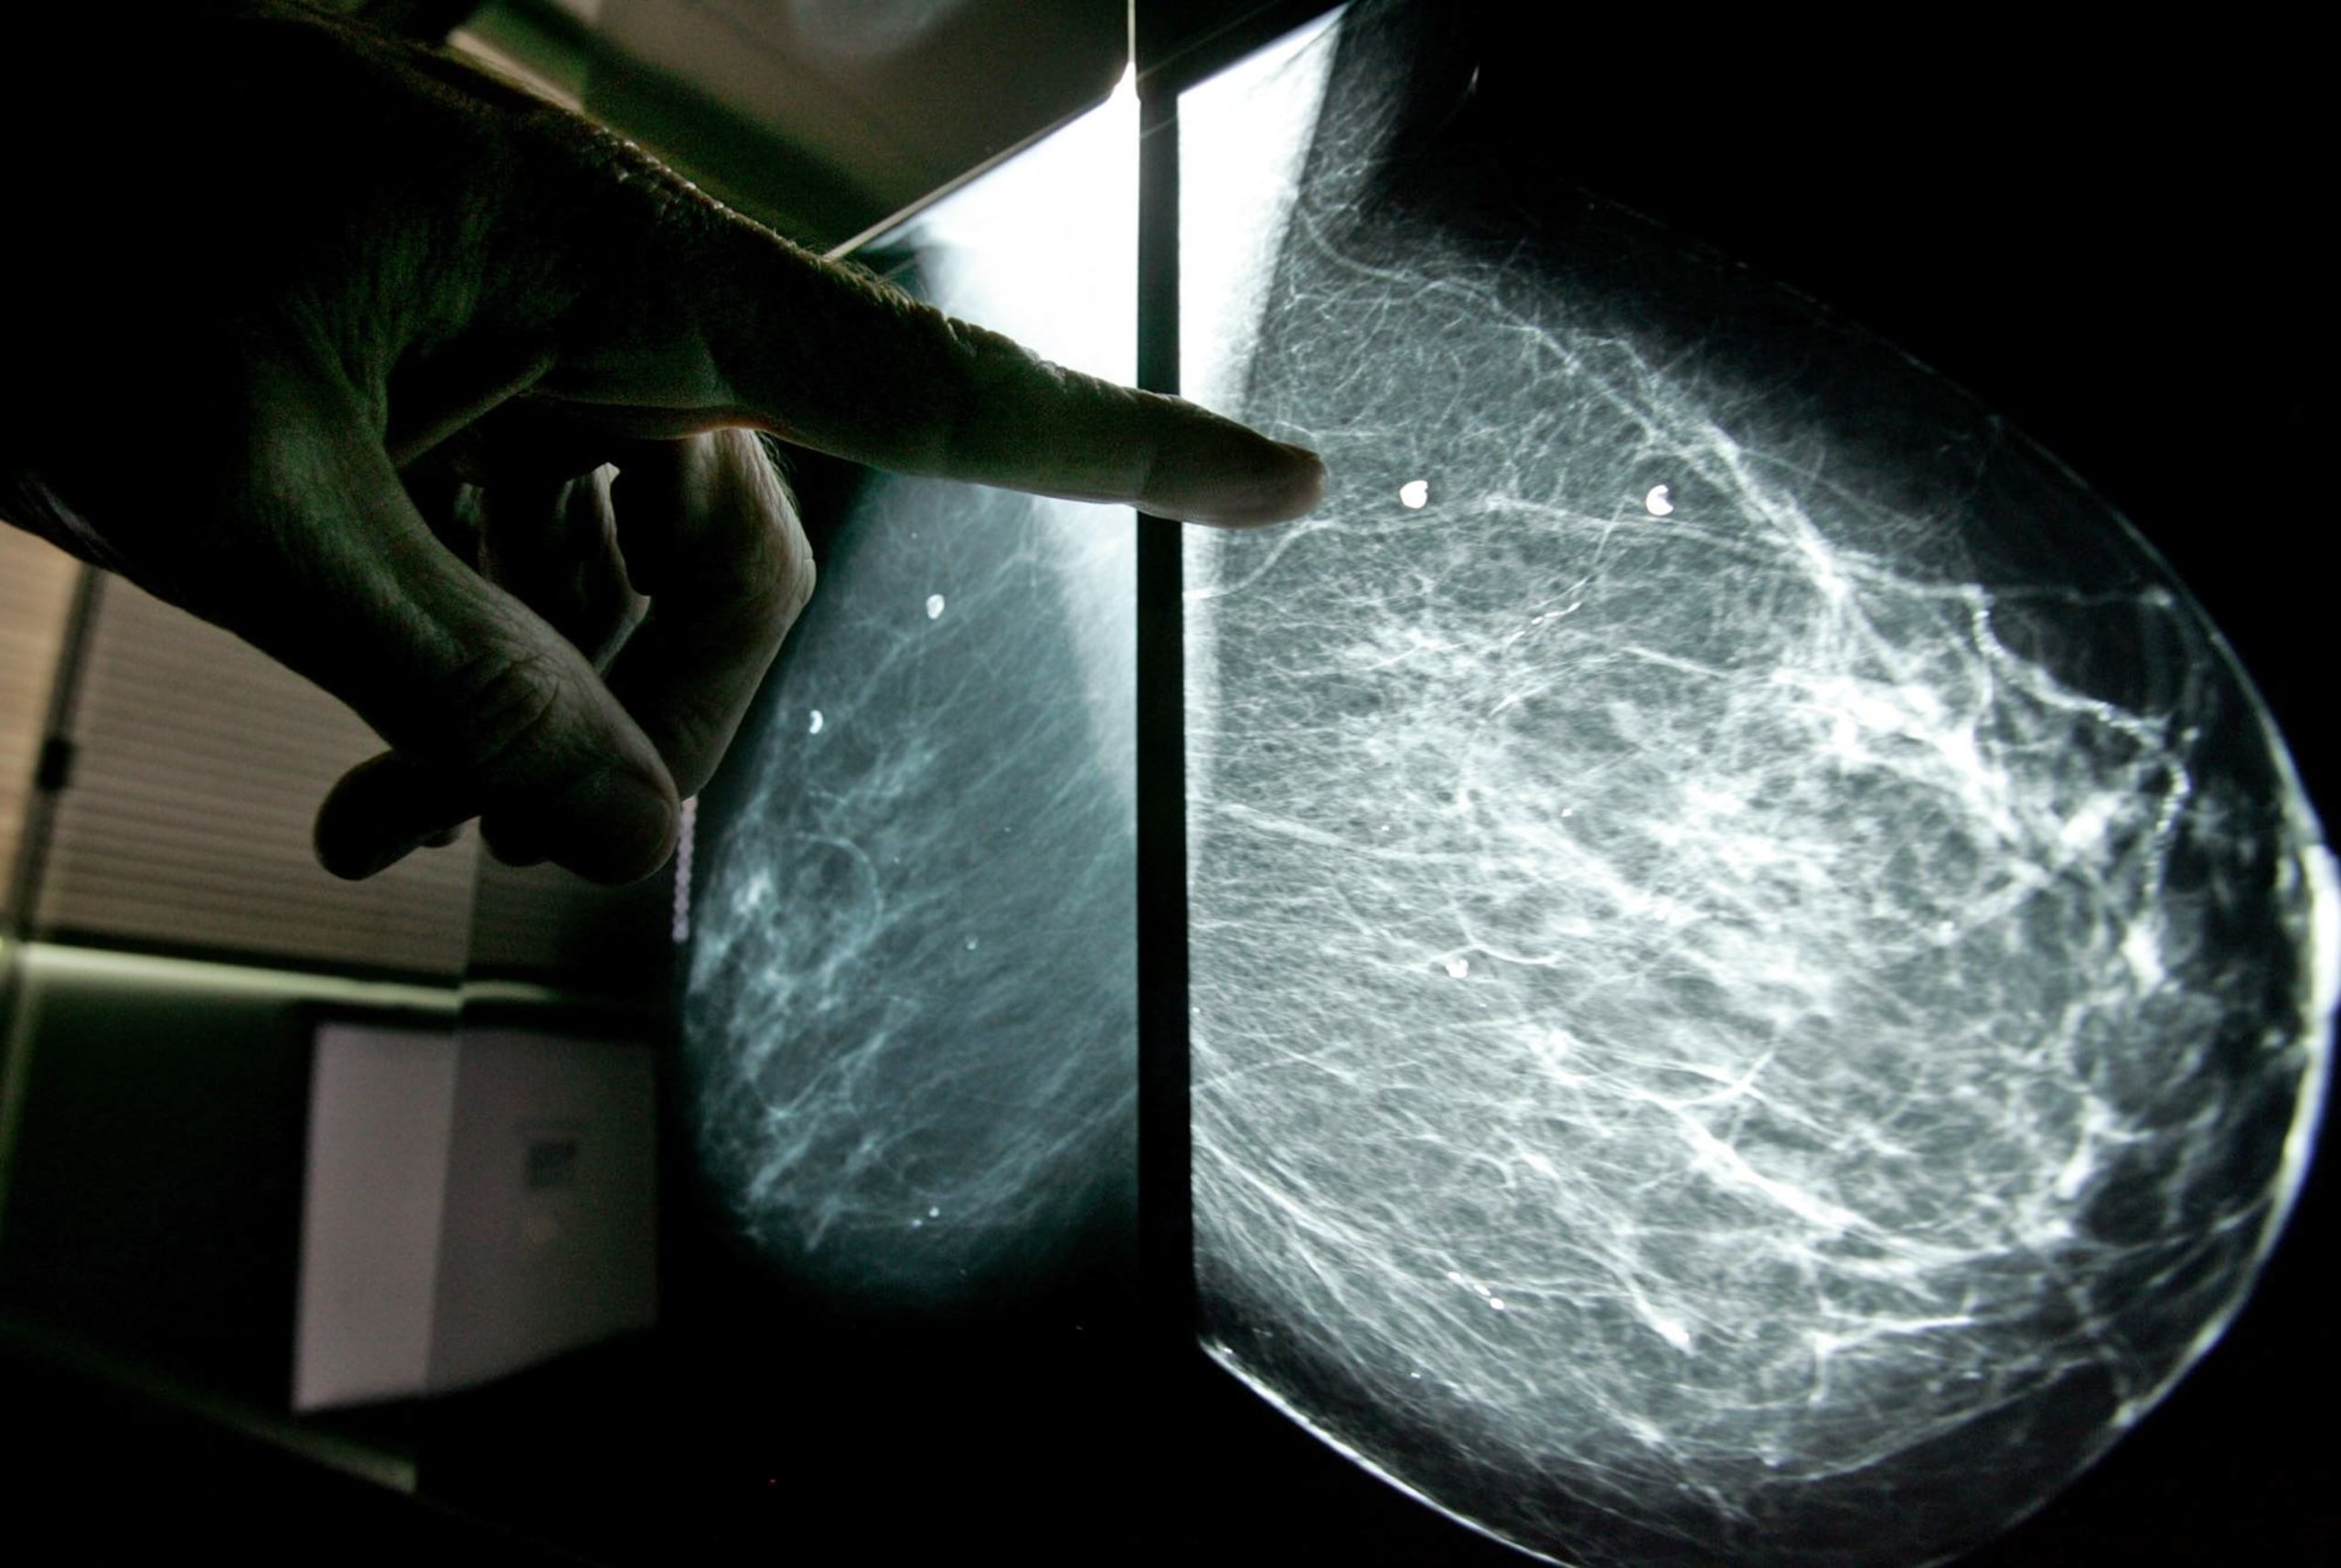

El cáncer de mama es el más común y el más mortal en mujeres, mientras que el de pulmón ocupa el primer lugar en ambos casos para los hombres.

La agencia sanitaria de la ONU alertó sobre las graves desigualdades que persisten en cuanto a rápido diagnóstico y tratamiento del cáncer entre regiones más y menos desarrolladas, algo que es especialmente notable en el cáncer de mama.

Mientras en los países más desarrollados se calcula que una de cada 12 mujeres será diagnosticada con ese tipo de cáncer a lo largo de su vida pero sólo una de cada 71 fallecerá, en las economías más pobres, donde el diagnóstico es mucho más bajo (una de cada 27) las probabilidades de fallecer por este tumor son mayores (1 de cada 48).